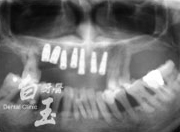

患者全口 X 光